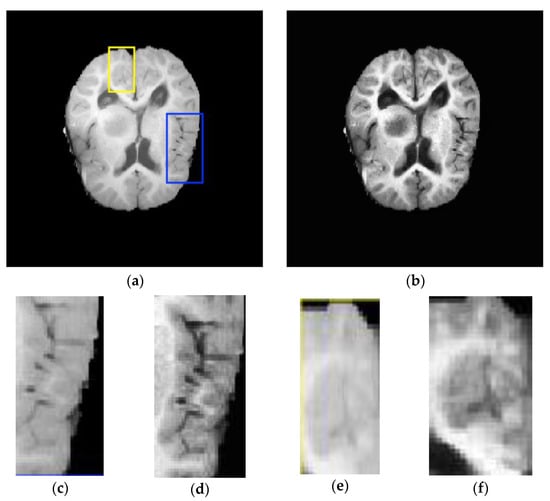

- Intensity inhomogeneity: This is due to the intensity of non-homogeneity of homogeneous tissues during contrast injection and the variations of spatial intensity over each dimension.

- Bias field: The bias field is another challenge faced during the process of brain segmentation in MR images, which is caused by the defects in the acquisition sequences or radiofrequency coil imperfections. The various biases associated with MR images include shading, noise, artifacts, and partial volume effects.

- Non-standardized intensity: The intensity of MR modalities depends on the magnetic fields and radio wave parameters, which are, in turn, influenced by the MR system hardware requirements.